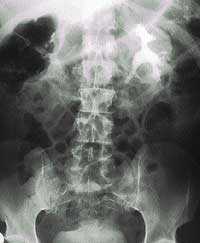

В табл. 1 приведены критерии для диагностики ИМП, в зависимости от лабораторных данных [3].